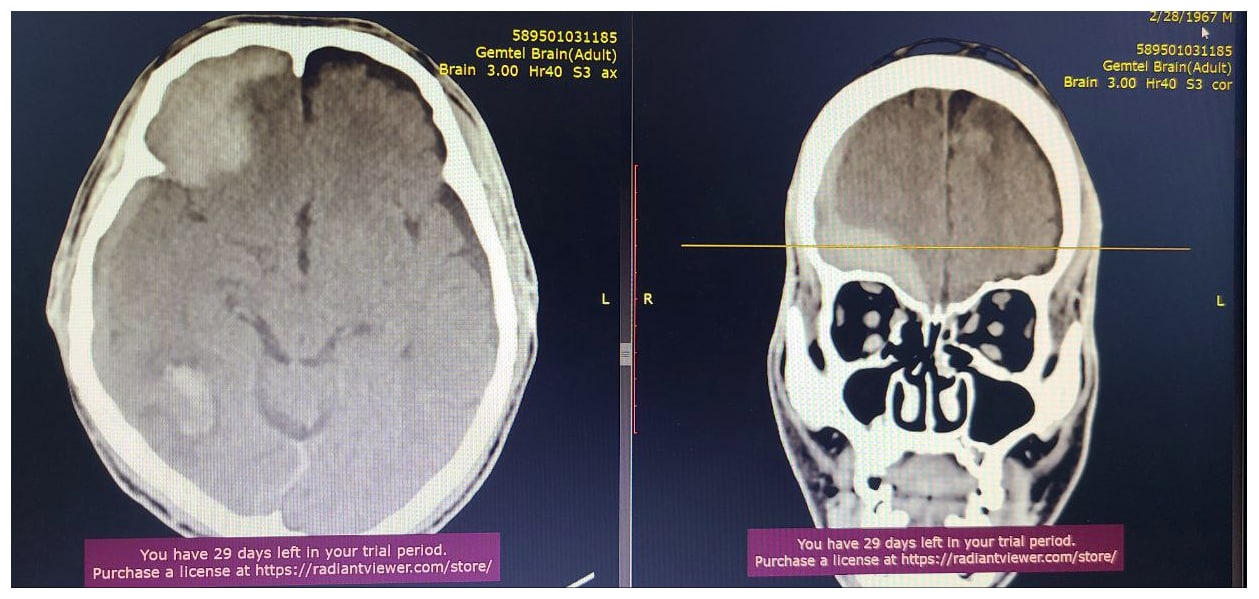

Гэмтэл Согог Судлалын Үндэсний төв Монголд анх удаа шагайн хиймэл үе солих мэс заслыг амжилттай нэвтрүүлсэн талаар бид өмнө нь мэдээлж байсан. Тэгвэл энэ удаад тус эмнэлгийн Гавал тархины гэмтлийн тасгийн эрхлэгч Л.Дагвадорж, их эмч Ж.Төгөлдөр, Б.Лхамсүрэн, Г.Ариунболд нарын мэс заслын баг Монголд анх удаа "Suction bovie" багажийн тусламжтайгаар гавал тархины хүнд гэмтэлтэй үйлчлүүлэгчийн гавал тархины хатуу хальсан доорх цусан хурааг дурангийн аргаар авах мэс заслыг амжилттай хийж нэвтрүүллээ.

Энэхүү орчин үеийн дэвшилтэт мэс заслыг нутагшуулснаар өвчтний биед хөнөөл багатай, жижиг зүслэгтэй, гавлын ясны дутмагшил бага үүсэх, хөдөлмөрийн чадвар алдалт бага зэрэг олон ач холбогдолтой юм.